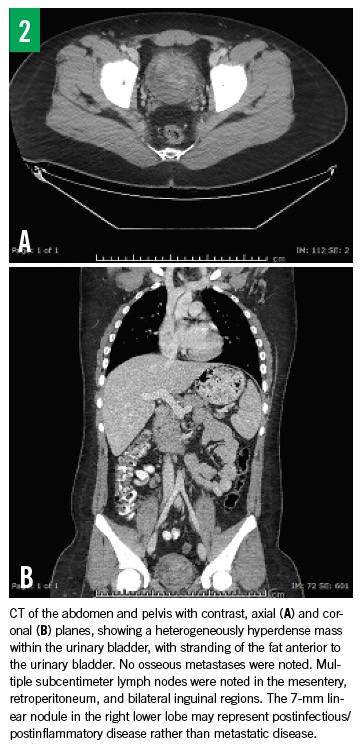

Results of repeated abdominal/pelvic CT with contrast (Figure 2) showed similar bladder findings and an additional lung nodule in the right lower lobe, which was linear and measured 7 mm—findings that were most consistent with a postinfectious or postinflammatory etiology. Nuclear medicine bone scan results did not show any lymph node enlargement or involvement.